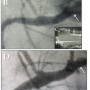

Stent implantation was categorized as: 1) too distal (> 1 mm distal to the angiographically determined ostium with > 30% residual stenosis) or requiring a second proximal stent (Figure 1); 2) too proximal (> 1 mm proximal to the angiographically determined ostium, particularly if the ostium could not be re-engaged with a guiding or diagnostic catheter; or 3) accurate (< 1 mm from the true ostium, with the ability to re-engage the ostium and with good reflux of the contrast on angiography) (Figure 2).

Some operators intentionally stick the proximal stent edge well into the aorta in order to prevent a distal miss. This, of course, almost always will create a proximal miss. Unfortunately, as demonstrated in our study, a proximal miss will result in a poor outcome for the patient, related to an inability to coaxially re-engage the ostium of a major coronary artery or graft again with either a diagnostic or guiding catheter in almost all cases. This may pose a greater risk than the restenosis that is often observed after a distal miss (Figure 1).